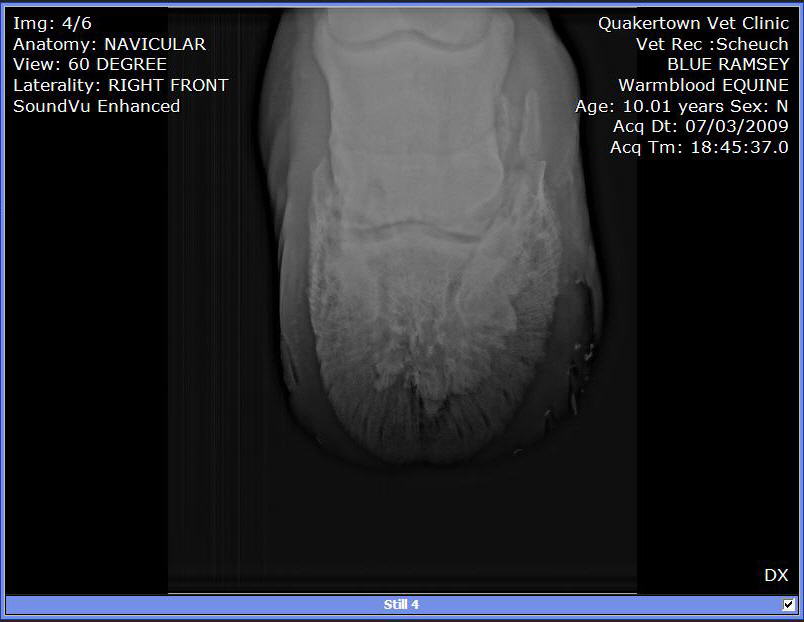

We put shoes on. Last week the farrier replaced them. He used a hoof tester checking of abscess or some reason for his slight limp. Since that day he as barely been able to walk. So, we called in the Vet to have him tested. A block in the heel helped him quite a bit. A block low in front and he was able to walk and trot without a limp.

X-rays:

I can see these are not images of a healthy hoof.

Among the many abnormalities the most important is the radiographs are clear for DJD of the coffin joint or what is often called low ringbone. No the hoof testers did not aggravate it, I suspect flexion of the joint during the exam did. You will find much information on this condition and what to expect at Diseases of Horses » Lameness » Diseases of the Lower Limb » Ringbone.

I can not read xrays to save my life, but I couldn't help feeling that this horse's foot was out of balance (from Image 3/6). I can't tell if its the way his foot is positioned on the plate, but he sure looks lopsided to me.

I would get his shoes off and get him back in balance ( to me he looks low on the outside and high on the inside. I'd be able to tell better if I could see the foot from the bottom to see which way the frog is leaning. I'd try to keep him as simple as possible at least for a few days to see how he handles being barefoot.

As rtrotter noted above the horse is either standing oddly or the foot is unbalanced from side to side in the above radiographs, careful management of balance and breakover could help this horse be as comfortable as possible.

Do the images suggest that the side bone has broken off?

No Guy it does not indicate it. Though we cannot say for sure this is a common appearance of a focal area of calcification for more on this see Diseases of Horses » Lameness » Diseases of the Hoof » Side Bone and the Collateral Cartilages.